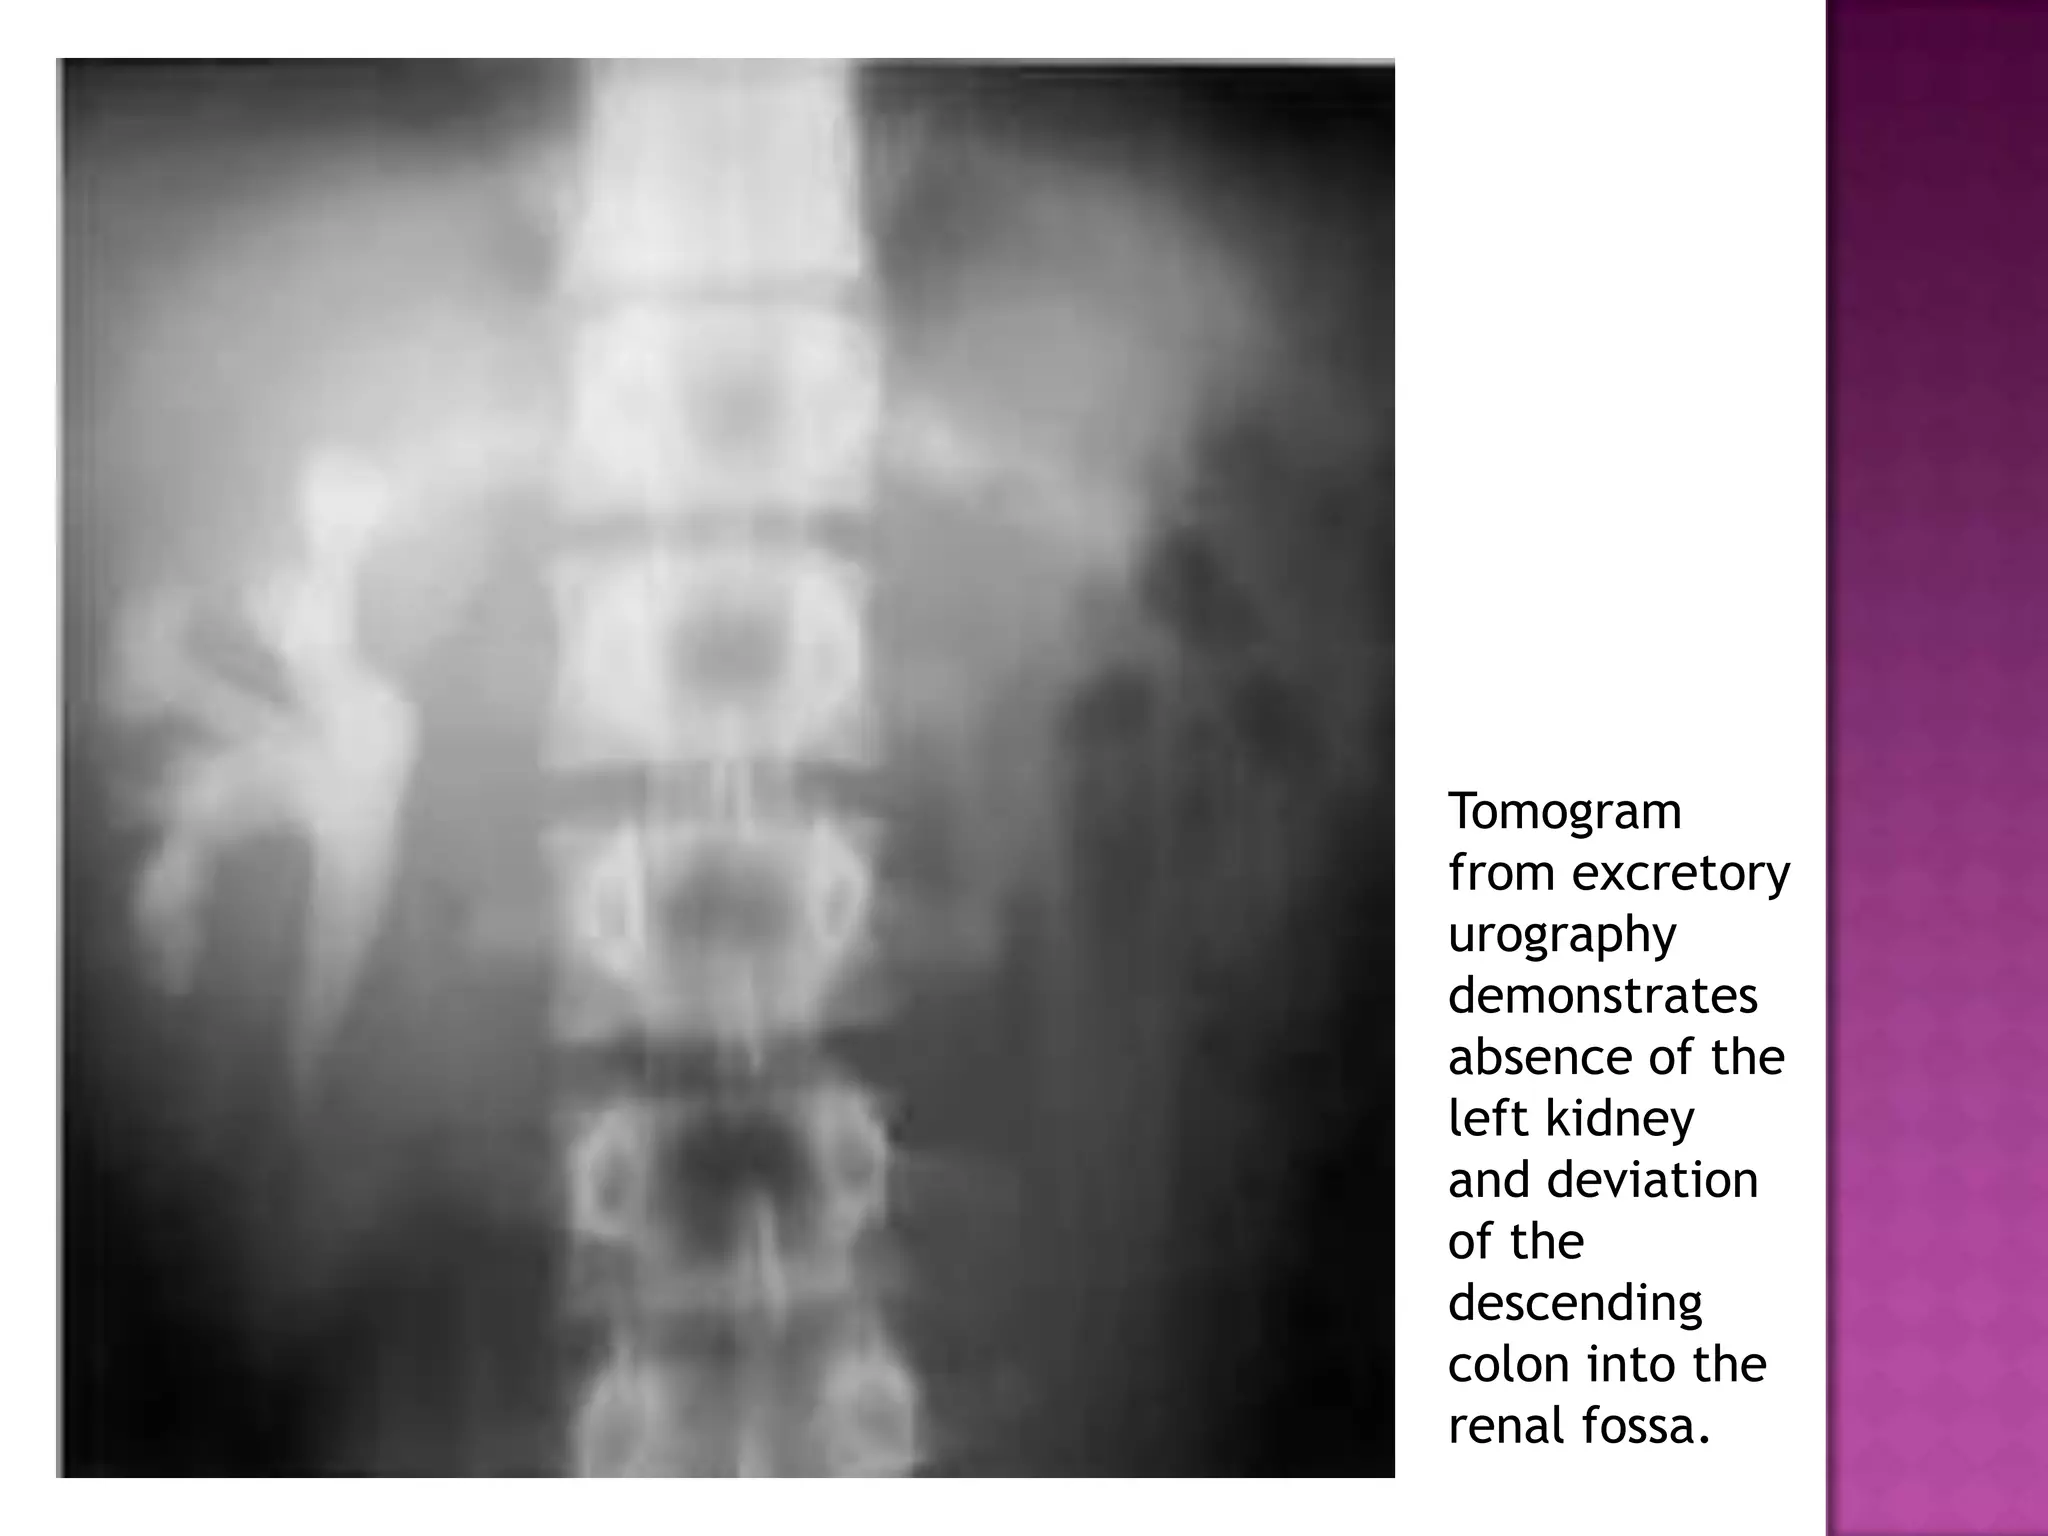

Tomogram

from excretory

urography

demonstrates

absence of the

left kidney

and deviation

of the

descending

colon into the

renal fossa.

Tomogram from excretory urography demonstrates absence ofthe left kidney and deviation of the descending colon into the renal fossa.